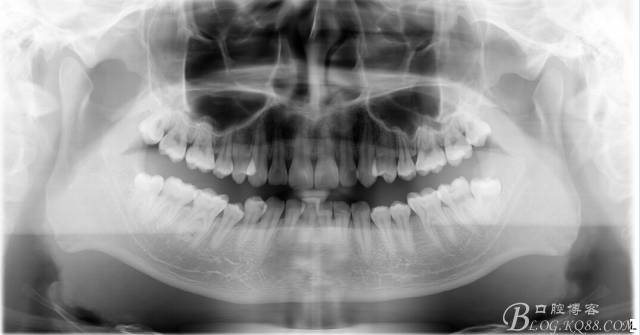

口腔檢查:37頰頜面齲洞,叩(+),探(+),冷熱測試與對照牙對比為敏感。17 27 47 均有不同程度齲壞,無明顯陽性體征。18 28 38 48 呈不同程度傾斜,38 48牙冠部分萌出。全口牙齒排列不整齊,口腔衛(wèi)生較差,牙石(++),部分牙齦發(fā)紅。X線檢查示37牙冠低密度影像累及牙髓,牙周間隙略增寬。

診斷:①37慢性牙髓炎 ②17 27 47頜面齲 ③18 28 38 48阻生牙 ④牙列不齊 ⑤牙齦炎